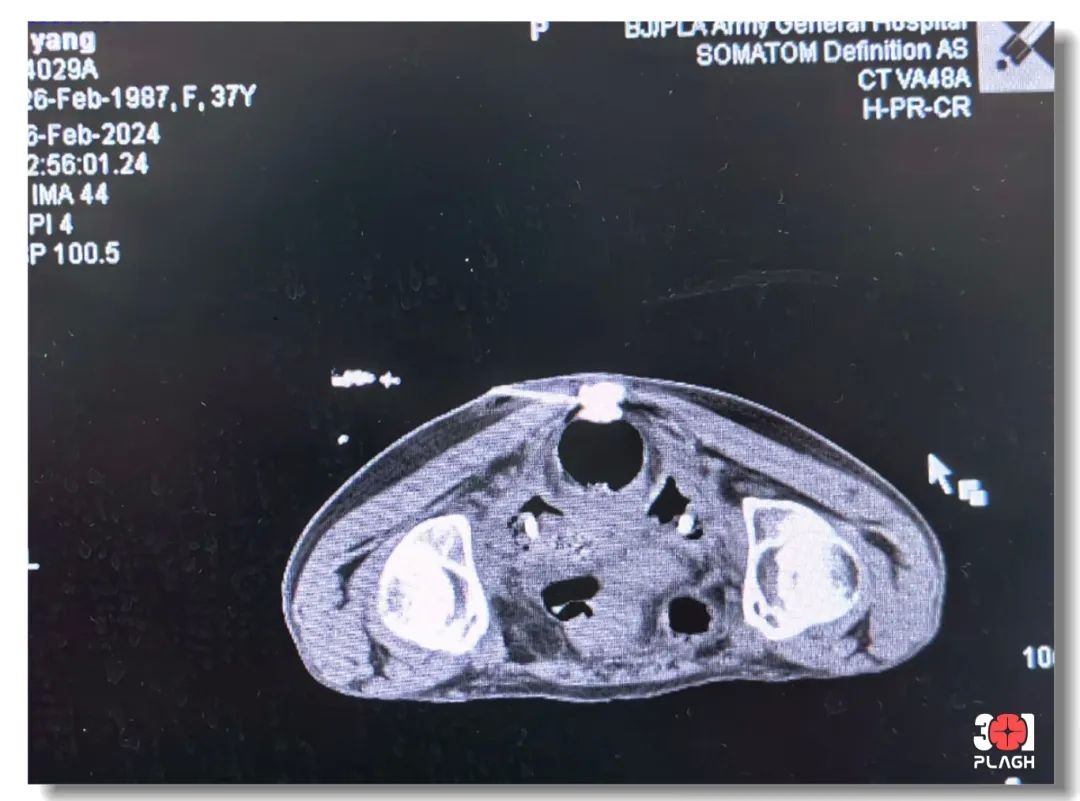

疼痛门诊刘刚主任为患者评估疼痛级别为8分,属重度疼痛,是肿瘤侵犯内脏神经(主要是奇神经节)所致的癌性内脏神经痛,目前服用的止痛药物剂量大、副作用不耐受,考虑到患者疼痛时间较长、程度较重、周围脏器浸润严重,需要进行微创介入治疗。为保证疼痛治疗效果和微创治疗安全,决定采用亚甲兰毁损+脉冲射频调控术。

术中,在CT精确引导下

借助三维重建技术

将射频热凝套管针

精准穿刺至奇神经节靶点位置

在注射造影剂进行影像学确认

基础上同时进行电生理测试

保证治疗的靶点精确性

又确保不影响运动神经